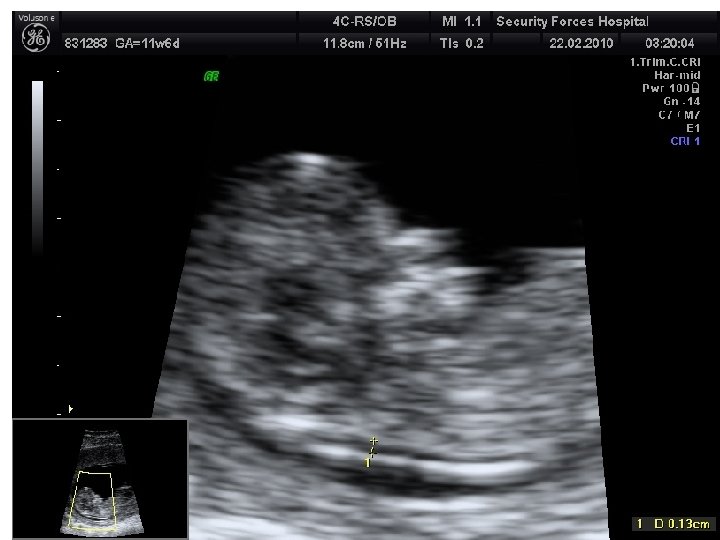

Screening for Down’s syndrome • • at 11– 14 weeks: Maternal age – Nuchal translucency (NT) – Combined test (NT + h. CG + PAPP-A) • • at 11– 14 weeks and then at 15– 20 weeks: – integrated test (combined test at 11– 14 weeks, followed by AFP, u. E 3 and inhibin A at 15– 20 weeks) • • at 15 – 20 weeks: – double test (h. CG, u. E 3) – triple test (h. CG, u. E 3, AFP) – quadruple test (h. CG, u. E 3, AFP, inhibin A) • – serum integrated test (PAPPA and h. CG at 11– 14 weeks, followed by AFP, u. E 3 and inhibin A at 15– 20 weeks).

Screening during Antenatal Care • 11 -14 w – – – – • • 20 w History for risk factors (GDM, Preeclampsia, psychatric ) Check weight, BP and urine + Asymptomatic bacteriuria Scan for dates, NT (and more? ) CBC +Red cell indices for haemoglobinopathies Blood group+ Rh+ RBC antibodies+ Hepatitis B+ HIV+ Syphilis+ Rubella Aneuploidy markers if possible – Scan for anomaly, soft marker for chromosomal abnormality, placenta, check uterine artery Dopplers and cervical length – Check weight, BP and urine 28 w – – Check weight, BP and urine Screen for gestational diabetes : 26 -28 weeks Anti D for Rh negative CBC + RBC antibodies

Screening for fetal anomalies • Ultrasound undertaken in first and second trimesters • Serum screening – alpha-fetoprotein (AFP).